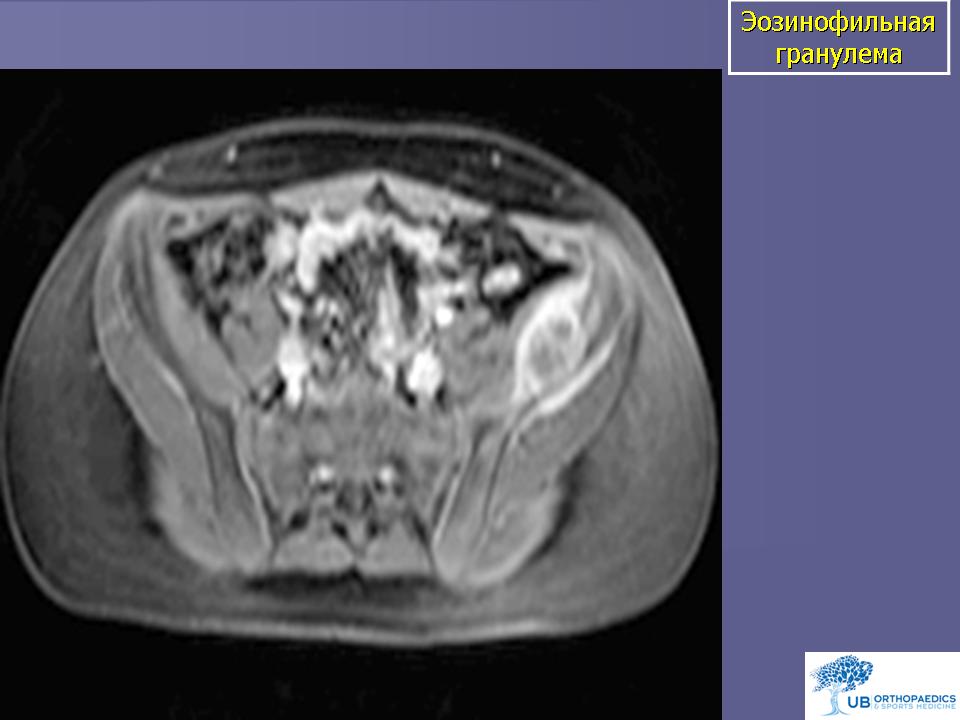

Эозинофильная гранулема. Это доброкачественное образование в кости, состоящее из гистиоцитов и эозинофилов, возникает в виде солитарной или множественной форм. В классическом варианте типичными для опухоли клетками являются гистиоциты, содержащие гранулы Лангерганса. Эозинофильная гранулема чаще поражает детей, реже встречается у лиц в возрасте старше 30 лет. Мультифокальный вариант отмечается у детей младшего возраста и может прогрессировать, что требует наравне с местным и системного лечения. Солитарные узлы всегда носят доброкачественный характер, заболевание не прогрессирует и имеет благоприятный прогноз. Клинически эозинофильная гранулема проявляется болью и ощущением дискомфорта в зоне поражения. Часто пальпаторно могут определяться мягкотканные массы. Рентгенологическая картина представлена в виде «выбитого» очага. Эозинофильная гранулема может поражать любую кость, однако чаще всего она встречается в костях черепа, в частности в челюсти, а также в костях таза, позвонках, других плоских костях. Опухоль может быстро расти, и рентгенологические признаки ее приобретают деструктивный характер. Больные с подозрением на эозинофильную гранулему должны тщательно обследоваться с использованием остеосцинтиграфии, обзорной рентгенографии костей скелета для исключения множественного поражения и в обязательном порядке - биопсии.

Эозинофильная гранулёма